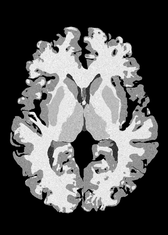

4.2 Registration to a 100 micron ex-vivo brain MRI volume

To showcase the efficacy of our method on real large scale images, we register a 250 in-vivo MRI image (Lüsebrink et al., 2017) to a 100 ex-vivo FLASH human brain volume (Edlow et al., 2019). This represents an inverse problem with more than 11.2B optimizable parameters (compared to 20M for clinical datasets), or 44.8GB of GPU memory. The entire problem does not fit on most GPUs, necessitating distributed multimodal registration. We optimize a composite transform - affine followed by a diffeomorphic mapping; details can be found in Section E.1. Multimodal deformable registration took 58 seconds on 8 NVIDIA A6000 GPUs, which is unprecedented at this resolution. Fig. 6 shows qualitative results, highlighting the ability to register highly detailed structures such as cerebellar white matter; these structures are not visible at macroscopic scales. The resultant advantages of performing registration at this scale can allow researchers to characterize the neuroanatomy at microscopic resolutions and allow morphometric analysis of cortical layers and subcortical nuclei among other structures.